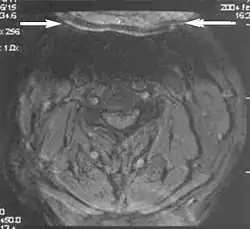

Metal artifacts

Metal artifacts occur at interfaces of tissues with different magnetic susceptibilities, which cause local magnetic fields to distort the external magnetic field. This distortion changes the precession frequency in the tissue leading to spatial mismapping of information. The degree of distortion depends on the type of metal (stainless steel having a greater distorting effect than titanium alloy), the type of interface (most striking effect at soft tissue-metal interfaces), pulse sequence and imaging parameters. Metal artifacts are caused by external ferromagnetics such as cobalt containing make-up, internal ferromagnetics such as surgical clips, spinal hardware and other orthopaedic devices, and in some cases, metallic objects swallowed by people with pica.[3] Manifestation of these artifacts is variable, including total signal loss, peripheral high signal and image distortion (Figs 3 and 4).[1] Reduction of these artifacts can be attempted by orientating the long axis of an implant or device parallel to the long axis of the external magnetic field, possible with mobile extremity imaging and an open magnet. Further methods used are choosing the appropriate frequency encoding direction, since metal artifacts are most pronounced in this direction, using smaller voxel sizes, fast imaging sequences, increased readout bandwidth and avoiding gradient-echo imaging when metal is present. A technique called MARS (metal artifact reduction sequence) applies an additional gradient, along the slice select gradient at the time the frequency encoding gradient is applied.